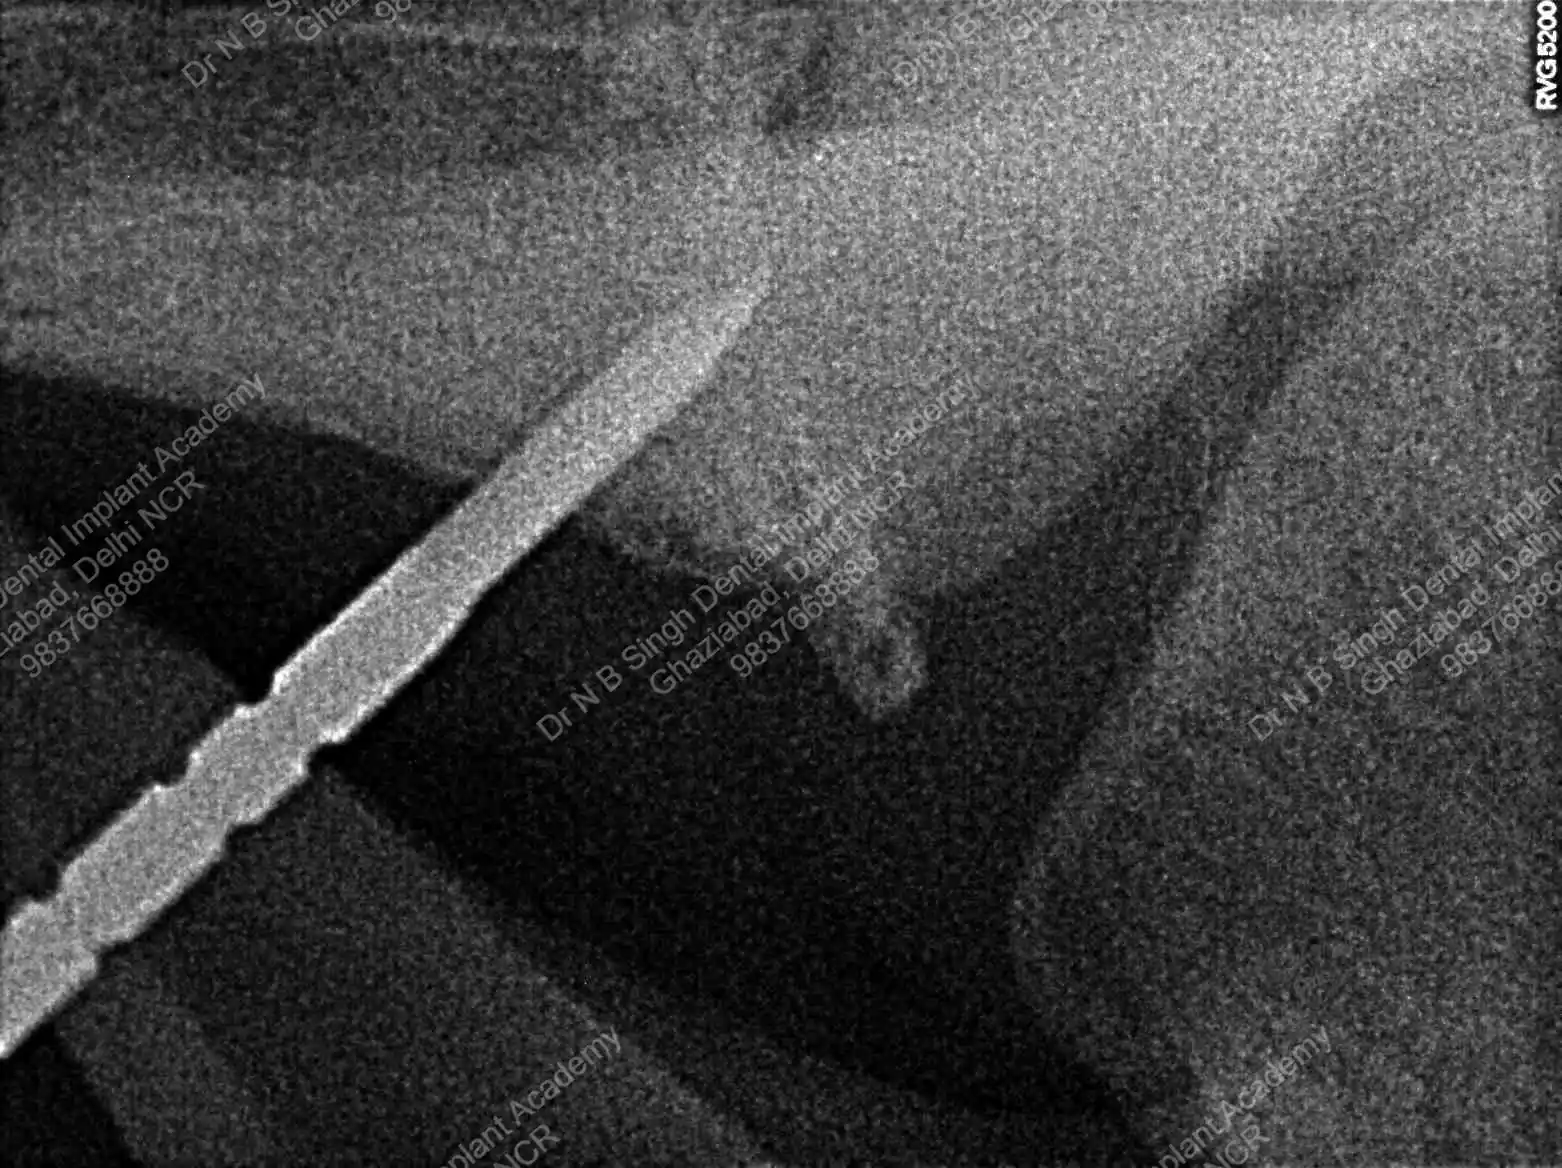

A008 Basal implants – af-qurs 1

Dr. N.B. Singh